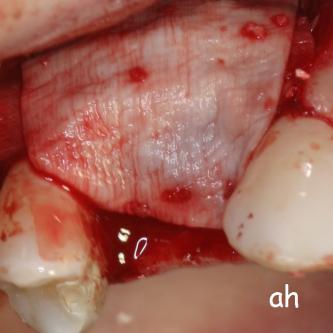

Exemple 11: Pendant l'implantation on remarque un manque d'os sur la partie externe, les spires de l'implant sont visibles.

Exemple 11: Une greffe d'os est effectuée afin de compenser l'épaisseur d'os manquante.

Exemple 11: Le tout est recouvert d'une membrane collagène.